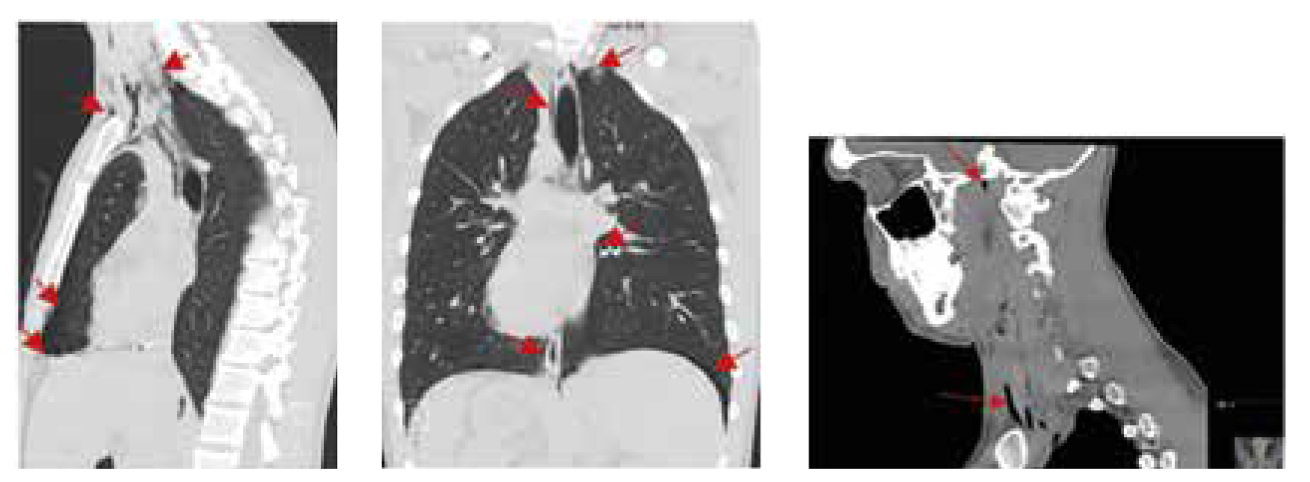

Fallbeskrivning Krampanfall och luftvägsruptur med pneumotorax och pneumomediastinum efter inhalation av lustgas från fyra patroner